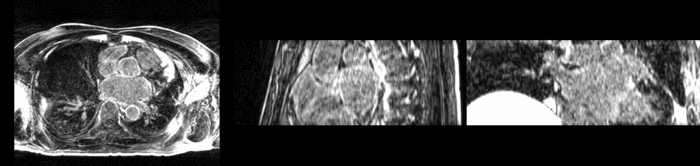

Top) Pre-ablation. Bottom) Post-ablation.

The pre and post-ablation images are shown below. The data dimensions are 320x320x20 for the pre-ablation, and 288x288x20 for the post-ablation. We observe differences in shape present due to respiration and subject placement. Furthermore, the ablation procedure has scarred the tissue of the atrium, which can be seen in bright white in the post-ablation image. As a result, the shape of the atrium has likely changed. For these reasons, this registration task is particularly challenging. The alignment before registration is shown below.